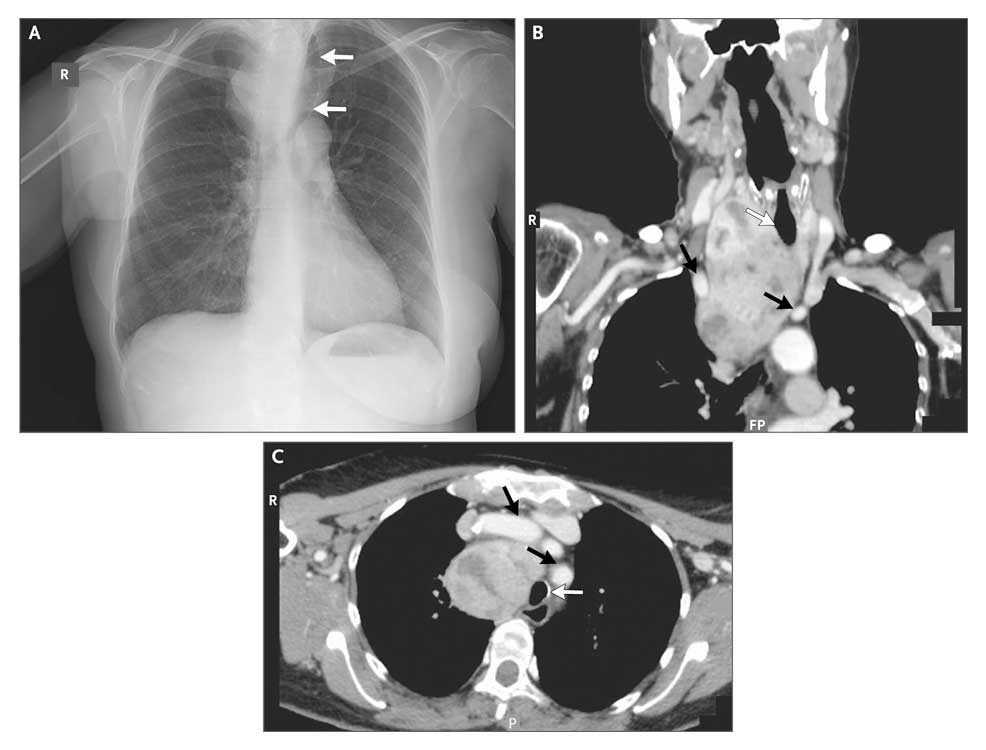

Chest radiography (Panel A) showed tracheal deviation (arrows). Cervical and mediastinal computed tomography (Panels B and C, respectively) showed a large goiter (8 by 6 by 10 cm) extending from the laryngeal cartilage into the mediastinum, displacing vascular structures (black arrows) and causing both compression and deviation of the trachea (white arrows).